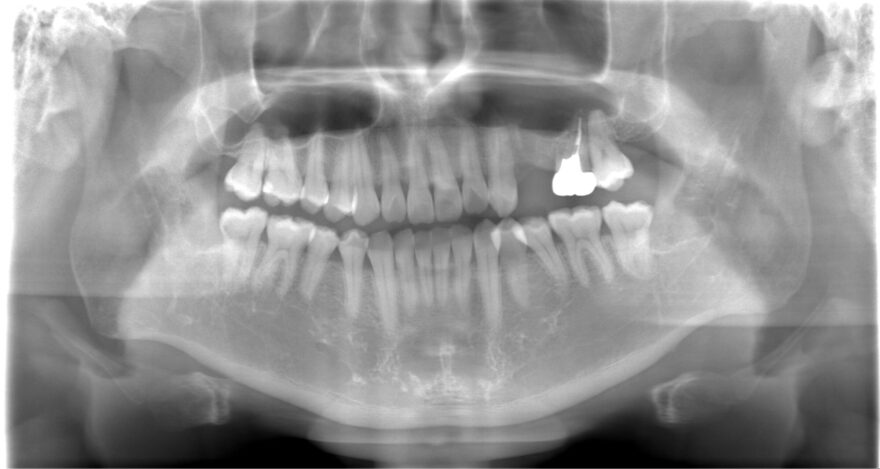

初診時のレントゲン写真

また銀歯(レントゲンで白く映っている歯)もグラグラしており、噛むと痛い状態でした。